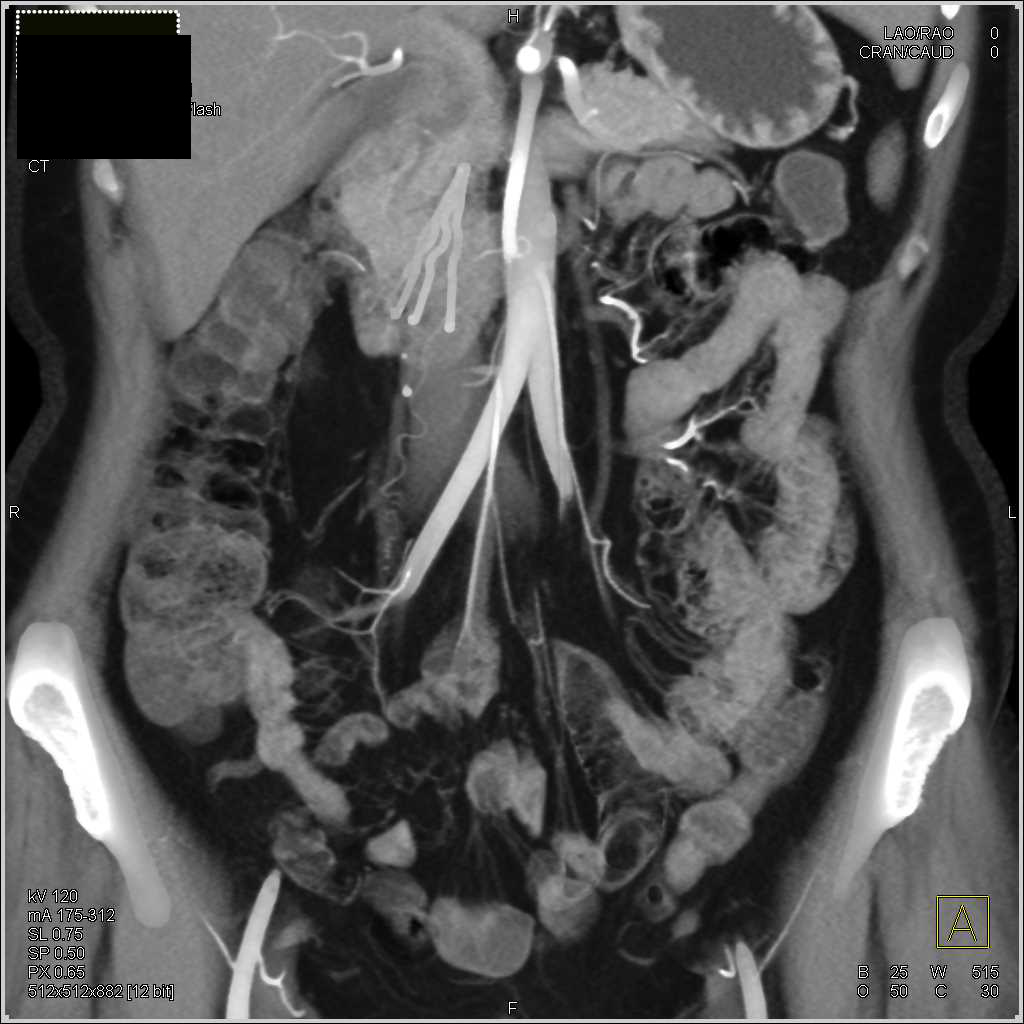

Autoimmune Pancreatitis